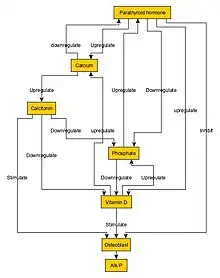

- Hypocalcemia

| Condition | Calcium | Phosphate | Alkaline phosphatase | Parathyroid hormone | Comments |

|---|---|---|---|---|---|

| Osteopenia | unaffected | unaffected | normal | unaffected | decreased bone mass |

| Osteopetrosis | unaffected | unaffected | elevated | unaffected | thick dense bones also known as marble bone |

| Osteomalacia and rickets | decreased | decreased | elevated | elevated | soft bones |

| Osteitis fibrosa cystica | elevated | decreased | elevated | elevated | brown tumors |

| Paget's disease of bone | unaffected | unaffected | variable (depending on stage of disease) | unaffected | abnormal bone architecture |

Normal bone growth is achieved by a balance between bone formation by osteoblasts and bone resorption (breakdown of bone matrix) by osteoclasts.[10] In osteopetrosis, the number of osteoclasts may be reduced, normal, or increased. Most importantly, osteoclast dysfunction mediates the pathogenesis of this disease.[11]

Osteopetrosis is caused by underlying mutations that interfere with the acidification of the osteoclast resorption pit, for example due to a deficiency of the carbonic anhydrase enzyme encoded by the CA2 gene.[12] Carbonic anhydrase is required by osteoclasts for proton production. Without this enzyme hydrogen ion pumping is inhibited and bone resorption by osteoclasts is defective, as an acidic environment is needed to dissociate calcium hydroxyapatite from the bone matrix. As bone resorption fails while bone formation continues, excessive bone is formed.[13]

It was the first genetic disease treated with hematopoietic stem cell transplantation (osteoclasts are derived from hematopoietic precursors). There is no cure, although curative therapy with bone marrow transplantion is being investigated in clinical trials. It is believed the healthy marrow will provide cells from which osteoclasts will develop.[4] If complications occur in children, patients can be treated with vitamin D. Gamma interferon has also been shown to be effective, and it can be associated to vitamin D. Erythropoetin has been used to treat any associated anemia. Corticosteroids may alleviate both the anemia and stimulate bone resorption. Fractures and osteomyelitis can be treated as usual.[4] Treatment for osteopetrosis depends on the specific symptoms present and the severity in each person. Therefore, treatment options must be evaluated on an individual basis. Nutritional support is important to improve growth and it also enhances responsiveness to other treatment options. A calcium-deficient diet has been beneficial for some affected people.[4]

- Vitamin D (calcitriol) appears to stimulate dormant osteoclasts, which stimulates bone resorption